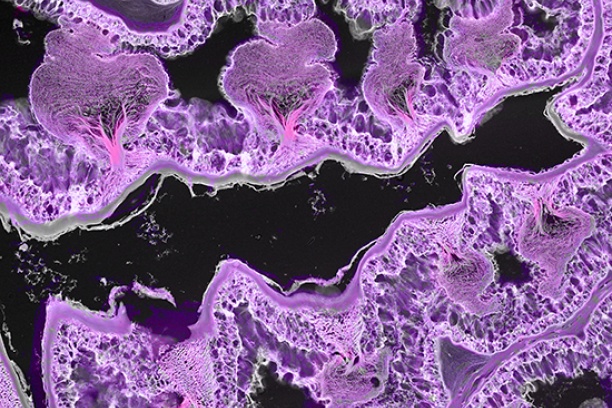

The Digital Histology Shared Resource provides large-scale digital archiving and quantitative analysis of histologic, immunohistochemical and immunofluorescence staining of tissue sections and tissue microarrays. Two Aperio Versa automated scanning microscopes, and Aperio AT2 and a Leica SCN400 Slide Scanner deliver solutions for high-resolution imaging in both bright field and fluorescence. All instruments have high-capacity robotic autoloading (200 slides for the Aperio Versa and Aperio AT2 and 384 slides for the Leica SCN400) making them ideal for large slide cohorts and tissue microarrays. The associated software packages provide complex algorithms for unbiased, automated image analysis and quantitation of immunostaining in both bright field and fluorescence. In addition, these systems can be utilized as a permanent high-resolution solution for those who need archiving of histologic material. The DHSR hosts a convenient, web-based digital slide-viewing environment (Digital Slide Archive) for the rapid retrieval, review, annotation and image acquisition of scanned material. This easy to use digital slide box allows researchers to share images among colleagues from any web browser while remaining in a digitally secure environment. Expert assistance is offered in planning experiments and processing data in a consistent, objective, and timely manner. The automated imaging and analysis performed in this core saves researchers and staff weeks of tedious work. An additional service offered by the DHSR is the creation of digital archives of critical and irreplaceable tissue samples, a benefit only feasible due to the automated high-resolution imaging of whole 25 mm x 75 mm microscope slides and 50 mm x 75 mm "double" slides.

The DHSR offers specialized microscopy assistance in addition to automated slide scanning and analysis, such as colony counting. The core is capable of high-resolution automated and semi-automated imaging and quantitation of a wide range of cell culture and tissue samples, from bacterial colonies to organoids. The GelCount• system by Oxford Optronix scans and counts mammalian cells, yeast or bacterial colonies in a wide variety of Petri dish and cell culture plate formats. This system is designed for the detection, counting and characterization of stained/adherent mammalian cell colonies or of unstained/non-adherent colonies in soft agar or collagen assays, but also works very well for yeast and bacterial colonies. The software is fully trainable and can be programmed to recognize specific colony features. Detailed information such as diameter, area, density, and nearest neighbor is provided, as well as high-resolution images.